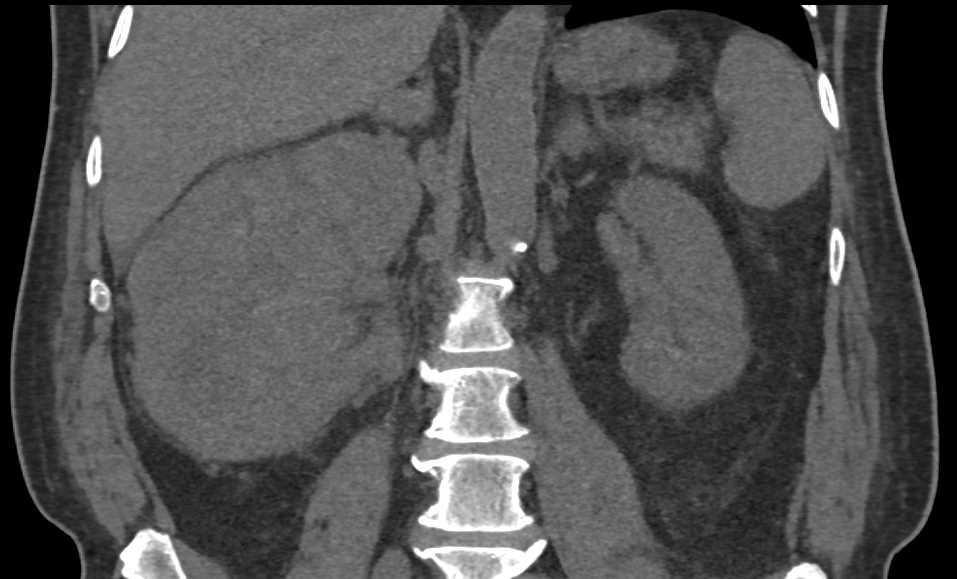

AV Fistulae Left Kidney